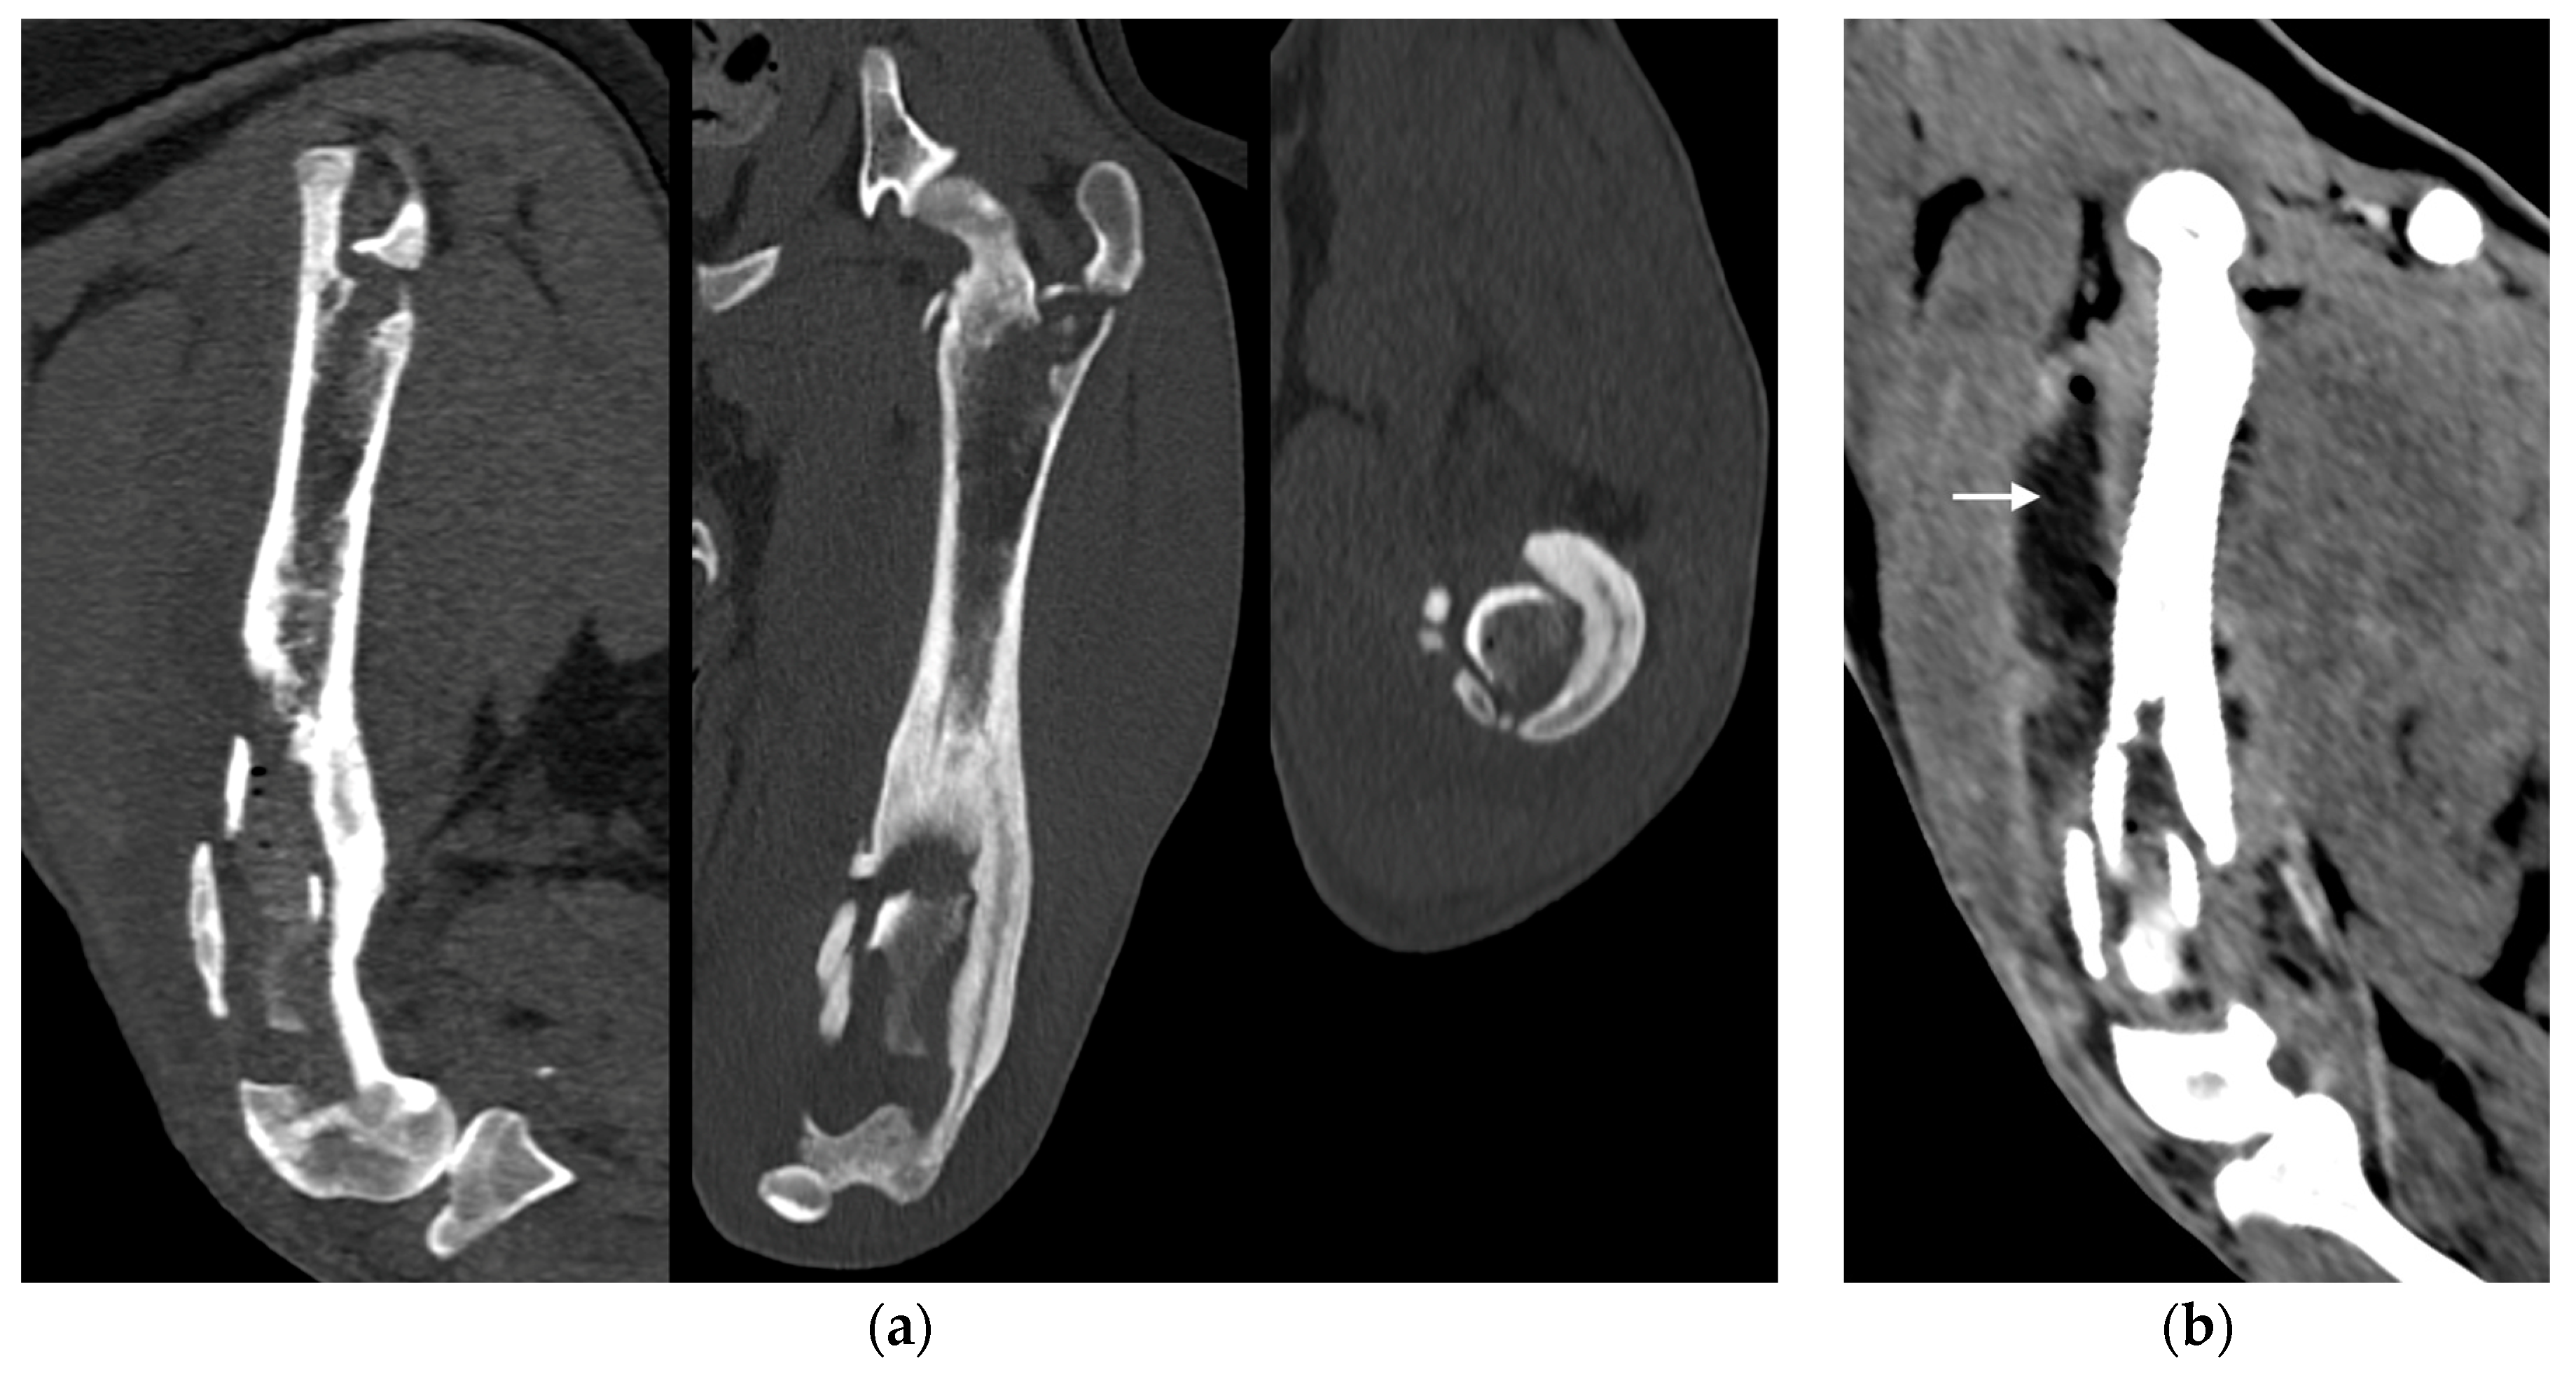

Under anesthesia, a computed tomography study (CT; Somatom Emotion 16, Siemens, Munich, Germany) of the hind limbs was performed. The tomographic images revealed medullary osteolysis of the metaphysis and the distal-middle third of the femoral diaphysis. In the metaphysis and the distal third of the femoral diaphysis, a bone sequestrum was found: a wide interruption of the cranio-medial cortical profile, with involvement of the femoral trochlea, was observed with corticomedullar fragment of 4 × 1.4 cm (length × width) medially dislocated at the level of the medullary cavity; the fragment was surrounded by a large hypodense halo. Secondary MPL and widespread subcutaneous and perifascial abscess lesions were also reported (Figure 3).

Figure 3. (a) Sagittal, frontal and transverse tomographic images of the metaphysis and the distal-middle third of the femoral diaphysis revealed medullary osteolysis, a wide interruption of the cranio-medial cortical profile with corticomedullar fragment of 4 × 1.4 cm (length × width) medially dislocated at the level of the medullary cavity (bone sequestrum) and an extensive periosteal reaction of the caudo-lateral cortex of the femoral distal diaphysis. (b) Widespread subcutaneous and perifascial abscess lesions were also reported (white arrow).